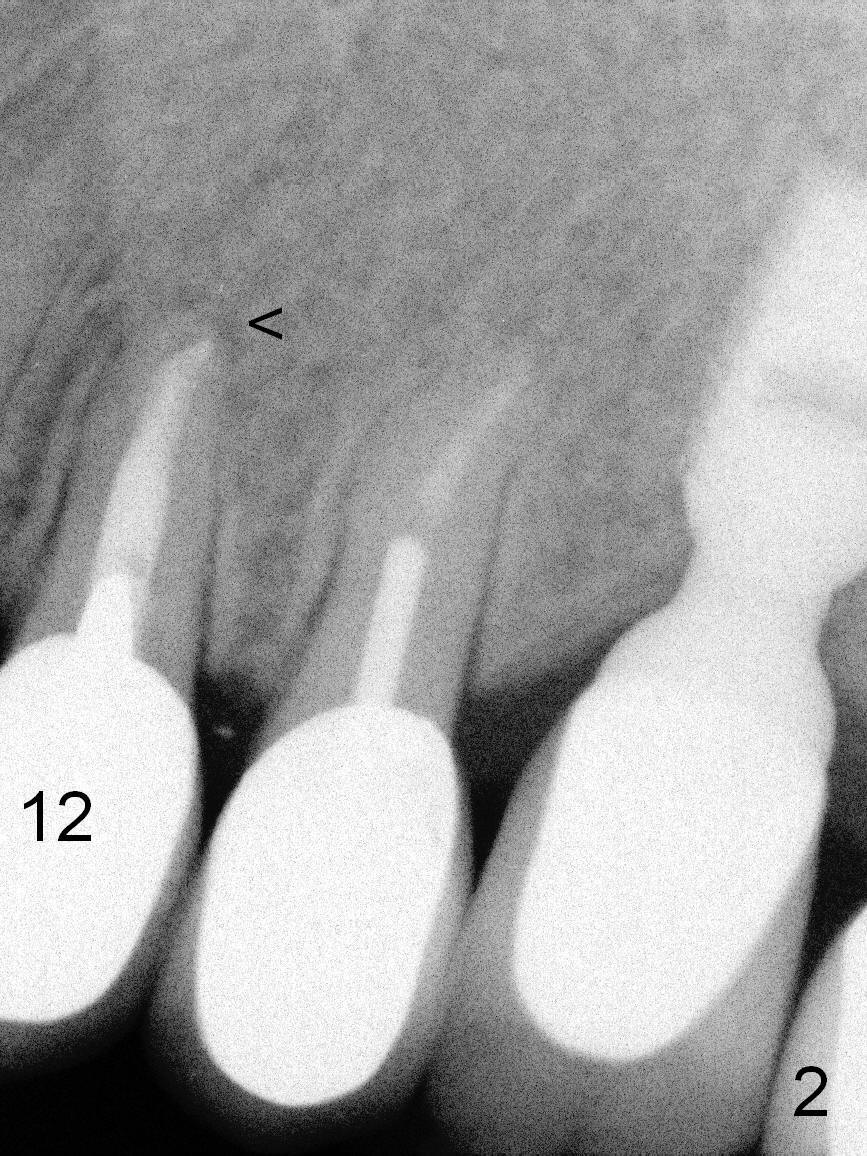

A 57-year-old lady had poor dentition, including periapical radiolucency of the tooth #12, 8 years ago (Fig.1 *, 2007). After comprehensive treatment, the pathology is apparently under control (Fig.2 <, 2011). CBCT shows the pathology not completely resolved (Fig.3,4, coronal section, 2012). Early this year, there was sign of crack tooth at #12 (Fig.5 arrowheads). Last Saturday she returned because of dislodgement of the crown and post. The tooth is found to be non salvageable.